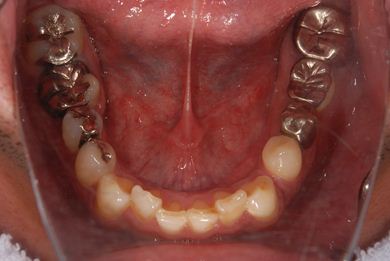

インプラントの症例写真 IMPLANT

抜歯即日スピードインプラント治療

| 性別/年齢 | 男性 / 36歳 | ||||||||||||||||||||||||||||||||

| 主訴 | 前歯が折れていてないので、インプラント治療を希望。 | ||||||||||||||||||||||||||||||||

| 治療内容 | インプラント1本(抜歯即日スピードインプラント)、ハイブリッドセラミッククラウン1本 | ||||||||||||||||||||||||||||||||

| 総治療費 | 257,250円 | ||||||||||||||||||||||||||||||||

| 治療期間 | 7ヶ月 |